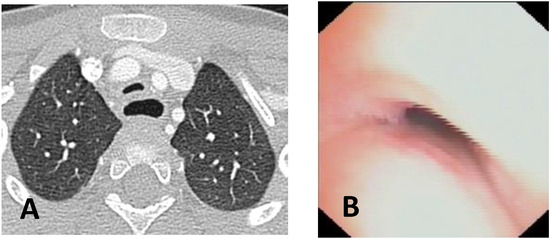

Diagnosis, Treatment, and Follow-Up of Tracheo/Bronchomalacia in Children: The Italian Multicenter Experience

by Angelo Florio, Michele Ghezzi, Francesca Rizzo, Paolo Del Greco, Katia Perri, Fabio Antonelli, Annalisa Gallizia, Francesco Santoro, Elena Ribera, Francesco Macchini, Michele Torre, Francesco Donati, Federica Lena, Vittorio Guerriero, Paola Borgia, Valerio Gentilino, Roberto D’Agostino, Federica Porcaro, Alessio Conte, Duino Meucci, Roberto Baggi, Michele Gaffuri, Pietro Salvati and Oliviero Saccoadd Show full author list remove Hide full author list

Children 2025, 12(11), 1511; https://doi.org/10.3390/children12111511 - 7 Nov 2025

Background: In pediatric age, the central airways are more flexible and mobile, with tracheal and bronchial walls easily tending to collapse, allowing partial or complete occlusion of the lumen: a situation described as tracheobronchomalacia (TBM). This is a condition that causes an increase [...] Read more.

Background: In pediatric age, the central airways are more flexible and mobile, with tracheal and bronchial walls easily tending to collapse, allowing partial or complete occlusion of the lumen: a situation described as tracheobronchomalacia (TBM). This is a condition that causes an increase in intrathoracic pressure that may accentuate airway collapse, and a biphasic or barking cough appears. Objectives: Although TBM is relatively frequent in pediatric age, the diagnostic criteria and subsequent treatment do not follow well-standardized criteria and often vary from pediatric center to center. Therefore, there is a need to standardize diagnostic procedures and the resulting medical or surgical treatments. Methods: We therefore organized a day of meetings to talk about TBM, inviting all Italian pediatricians and pediatric surgeons who diagnose and treat patients with this pathology on a daily basis. Results: This work, collecting all the meeting interventions, is a compendium that deals with all aspects of TBM, emphasizing the most correct criteria to diagnose and therefore best treat each pediatric patient with this clinical condition. We give particular emphasis to the need to perform static and dynamic videobronchoscopy (S/DVBS) to verify the patency of the tracheal lumen, so as to evaluate the severity of TBM. Conclusions: this work deals with TBM in all its diagnostic and treatment aspects and can be a valid help for all pediatricians who treat these patients. Full article

Show Figures

Figure 1